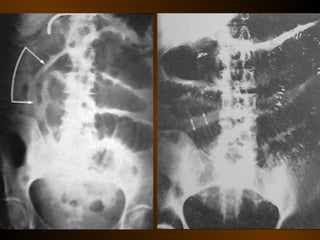

CĂNG GIÃN ỐNG TIÊU HÓA

• Căng giãn ruột non

PHÂN BIỆT

RUỘT NON – ĐẠI TRÀNG

• Các nếp Kerckring

• Nếp ngấn thanh mạc

• Khẩu kính

• Số lượng quai

• Phân bố các quai ruột

• Cao / rộng

• Chất cặn bã